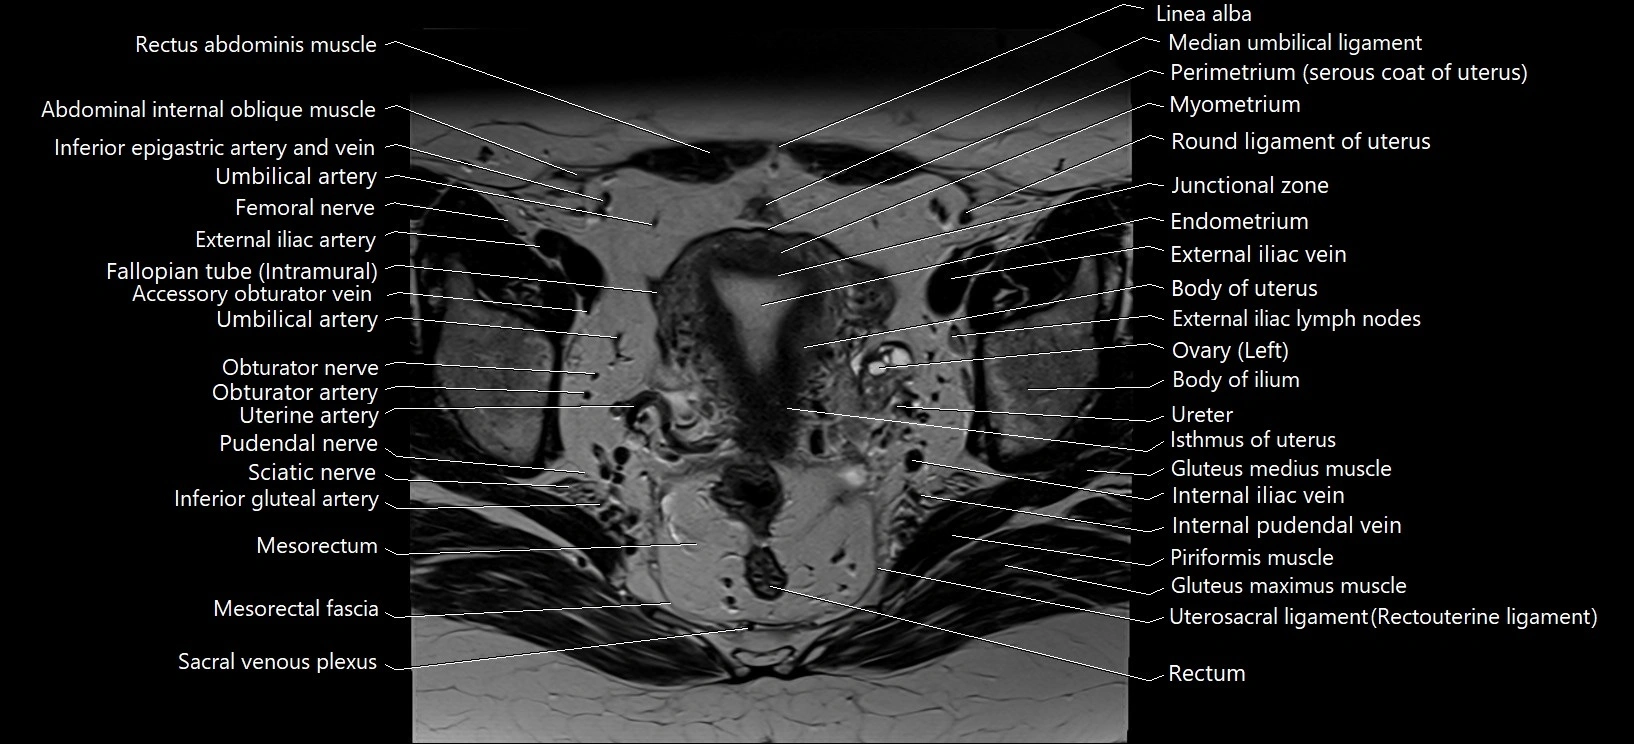

- Body of ilium

- External iliac lymph nodes

- External iliac vein

- Fallopian tube

- Junctional zone of uterus

- Median umbilical ligament

- Mesorectal fascia

- Mesorectum

- Myometrium of uterus

- Perimetrium of uterus

- Piriformis muscle

- Rectum

- Round ligament of uterus

- Umbilical artery

- Uterine artery

- Uterosacral ligament